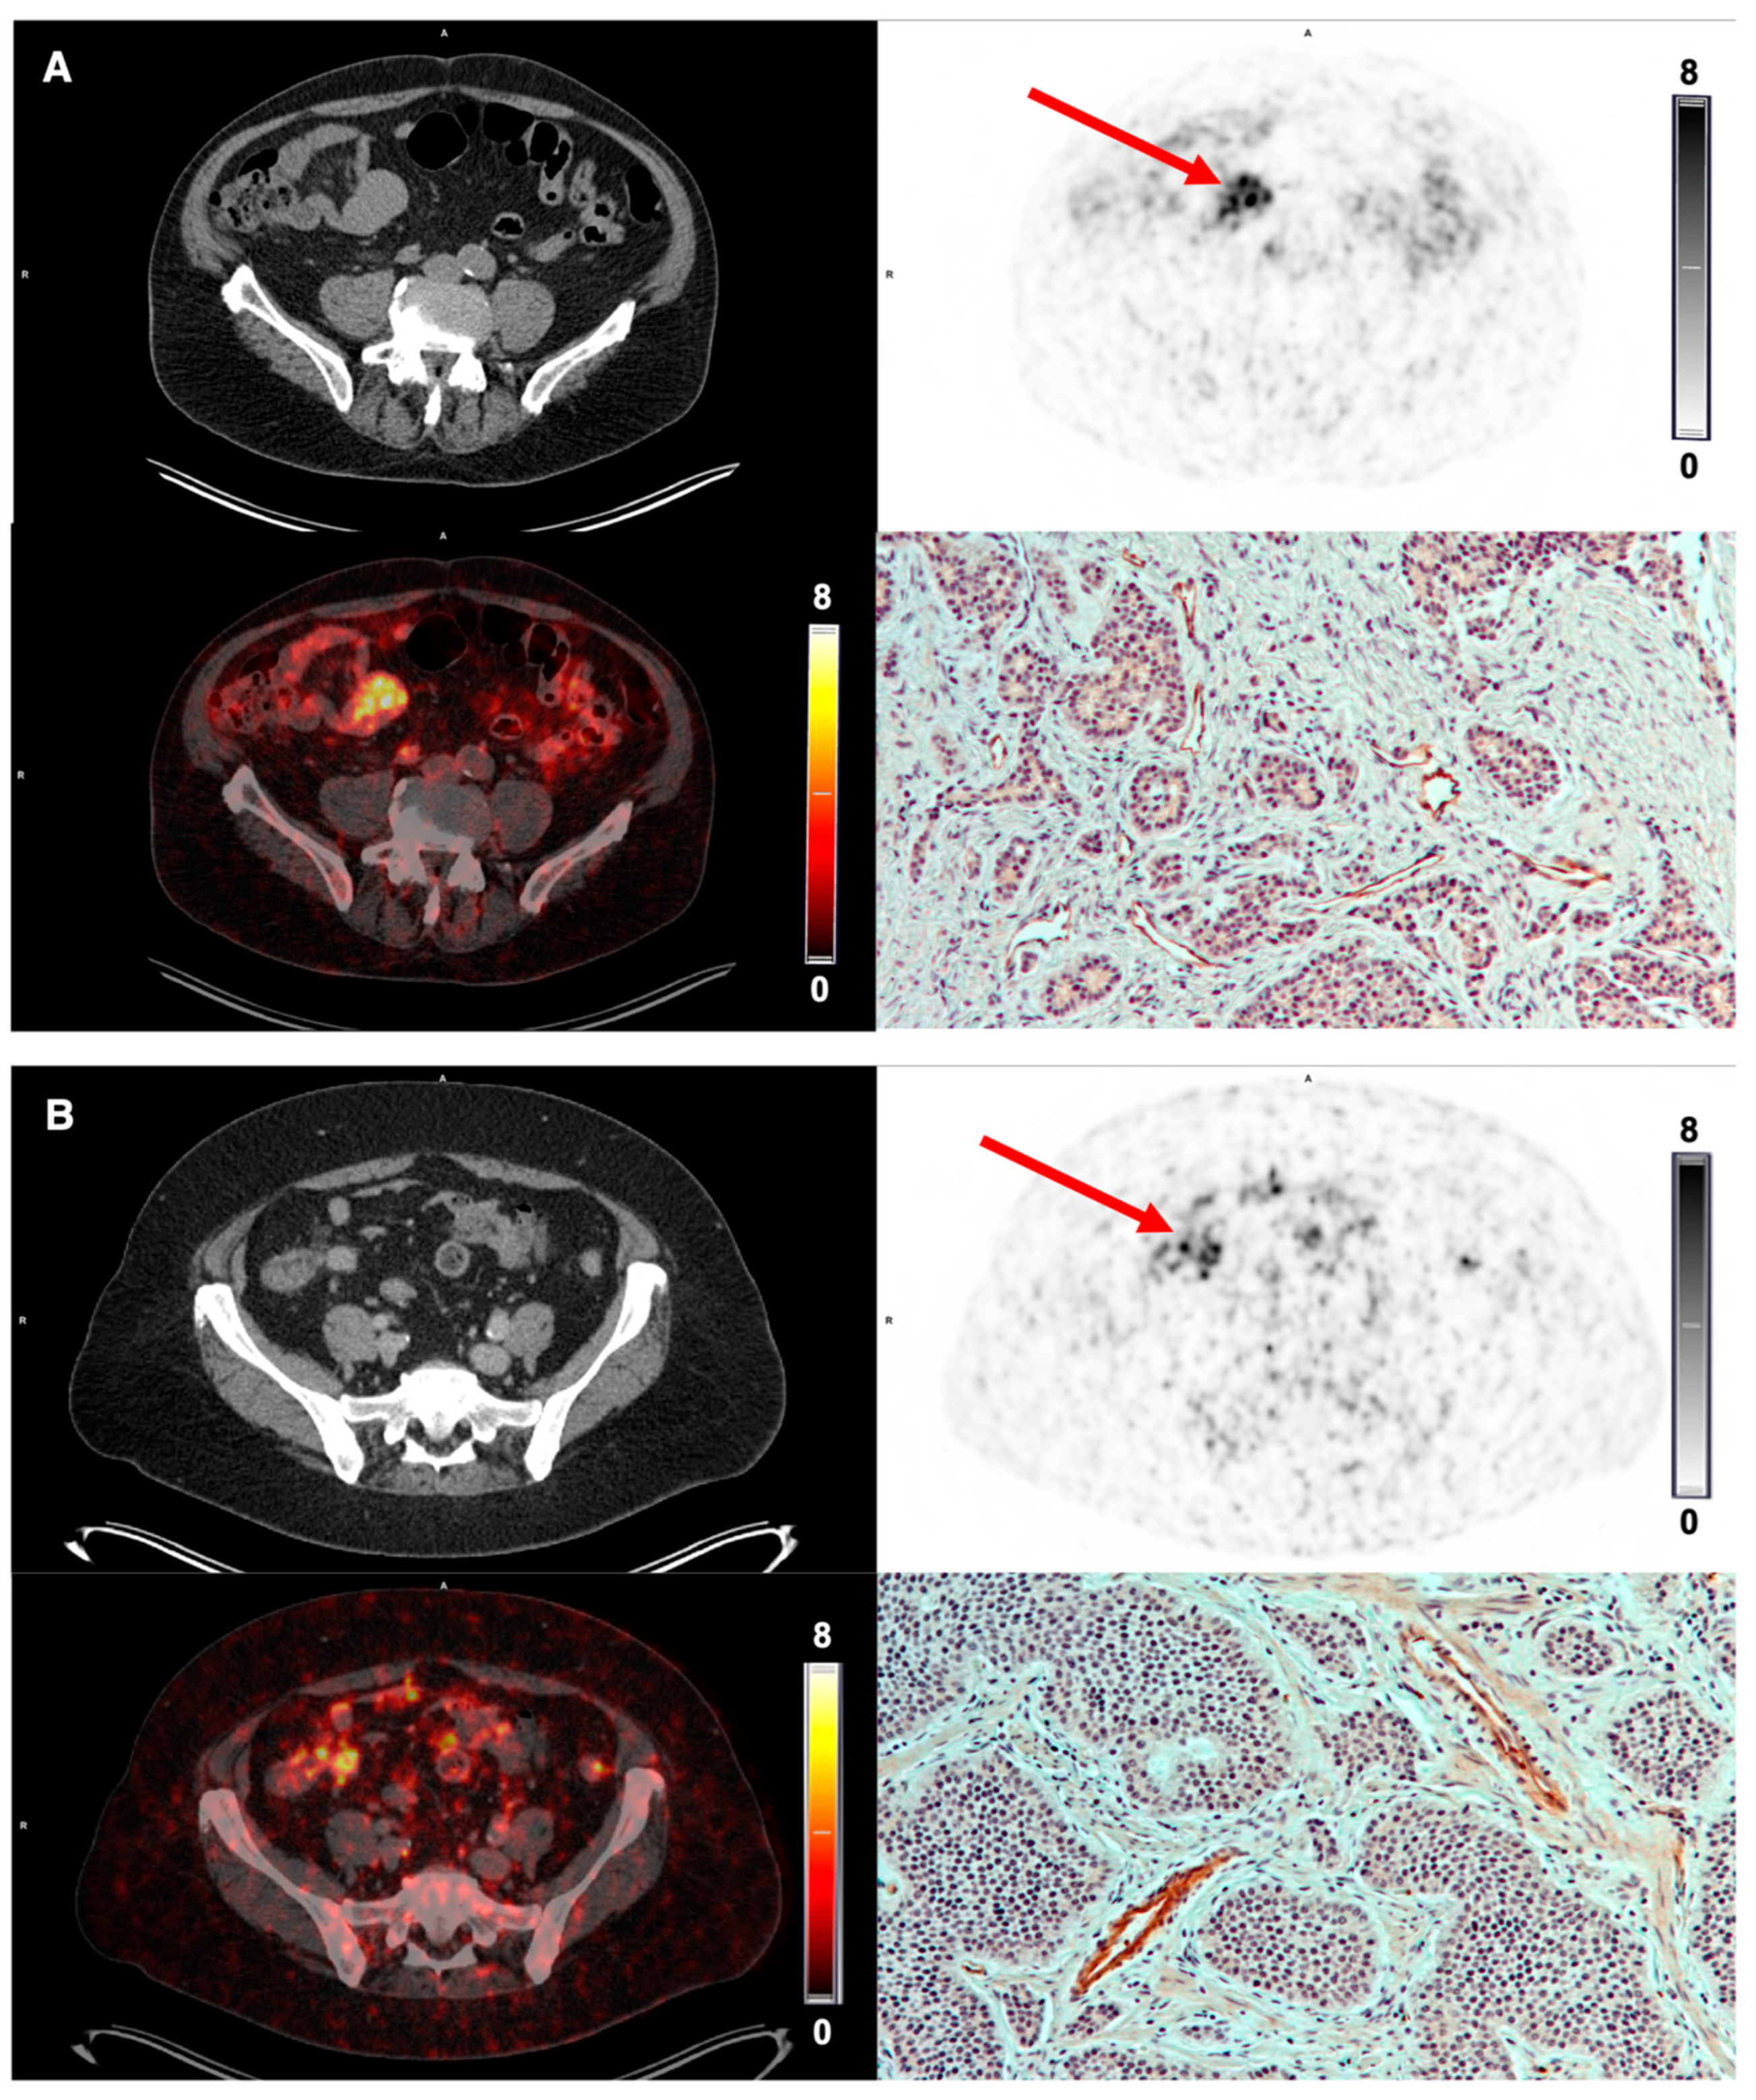

3.5. Tumor Uptake of [68Ga]Ga-NODAGA-E[c(RGDyK)]2 and Target Validation